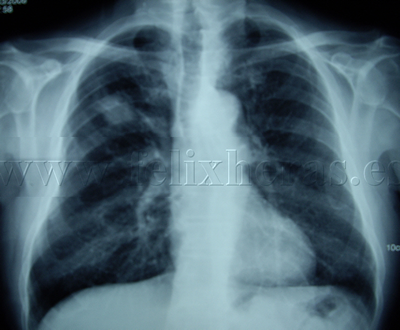

Cáncer de pulmón